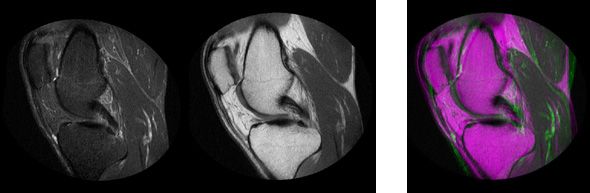

Automatic registration on multimodal medical images

Registering multimodal medical images

MATLAB supports images from a variety of modalities and provides built-in image registration workflows to integrate them.

This example shows how you can automatically align two volumetric data sets using intensity-based registration.